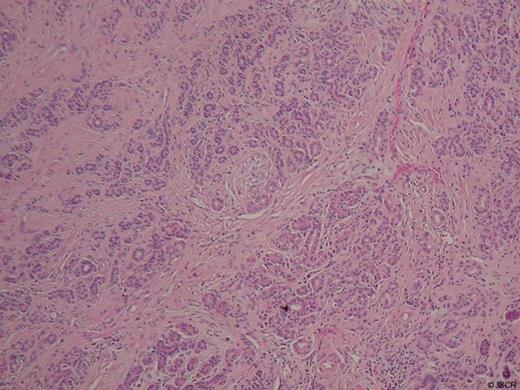

The histology of the resected specimen was reported as showing intramural benign gland hyperplasia within the distal CBD and ampulla (Figure 5).

Histology at x100 magnification demonstrating glandular lobules of duct-like structures within fibrous stroma of the ampulla